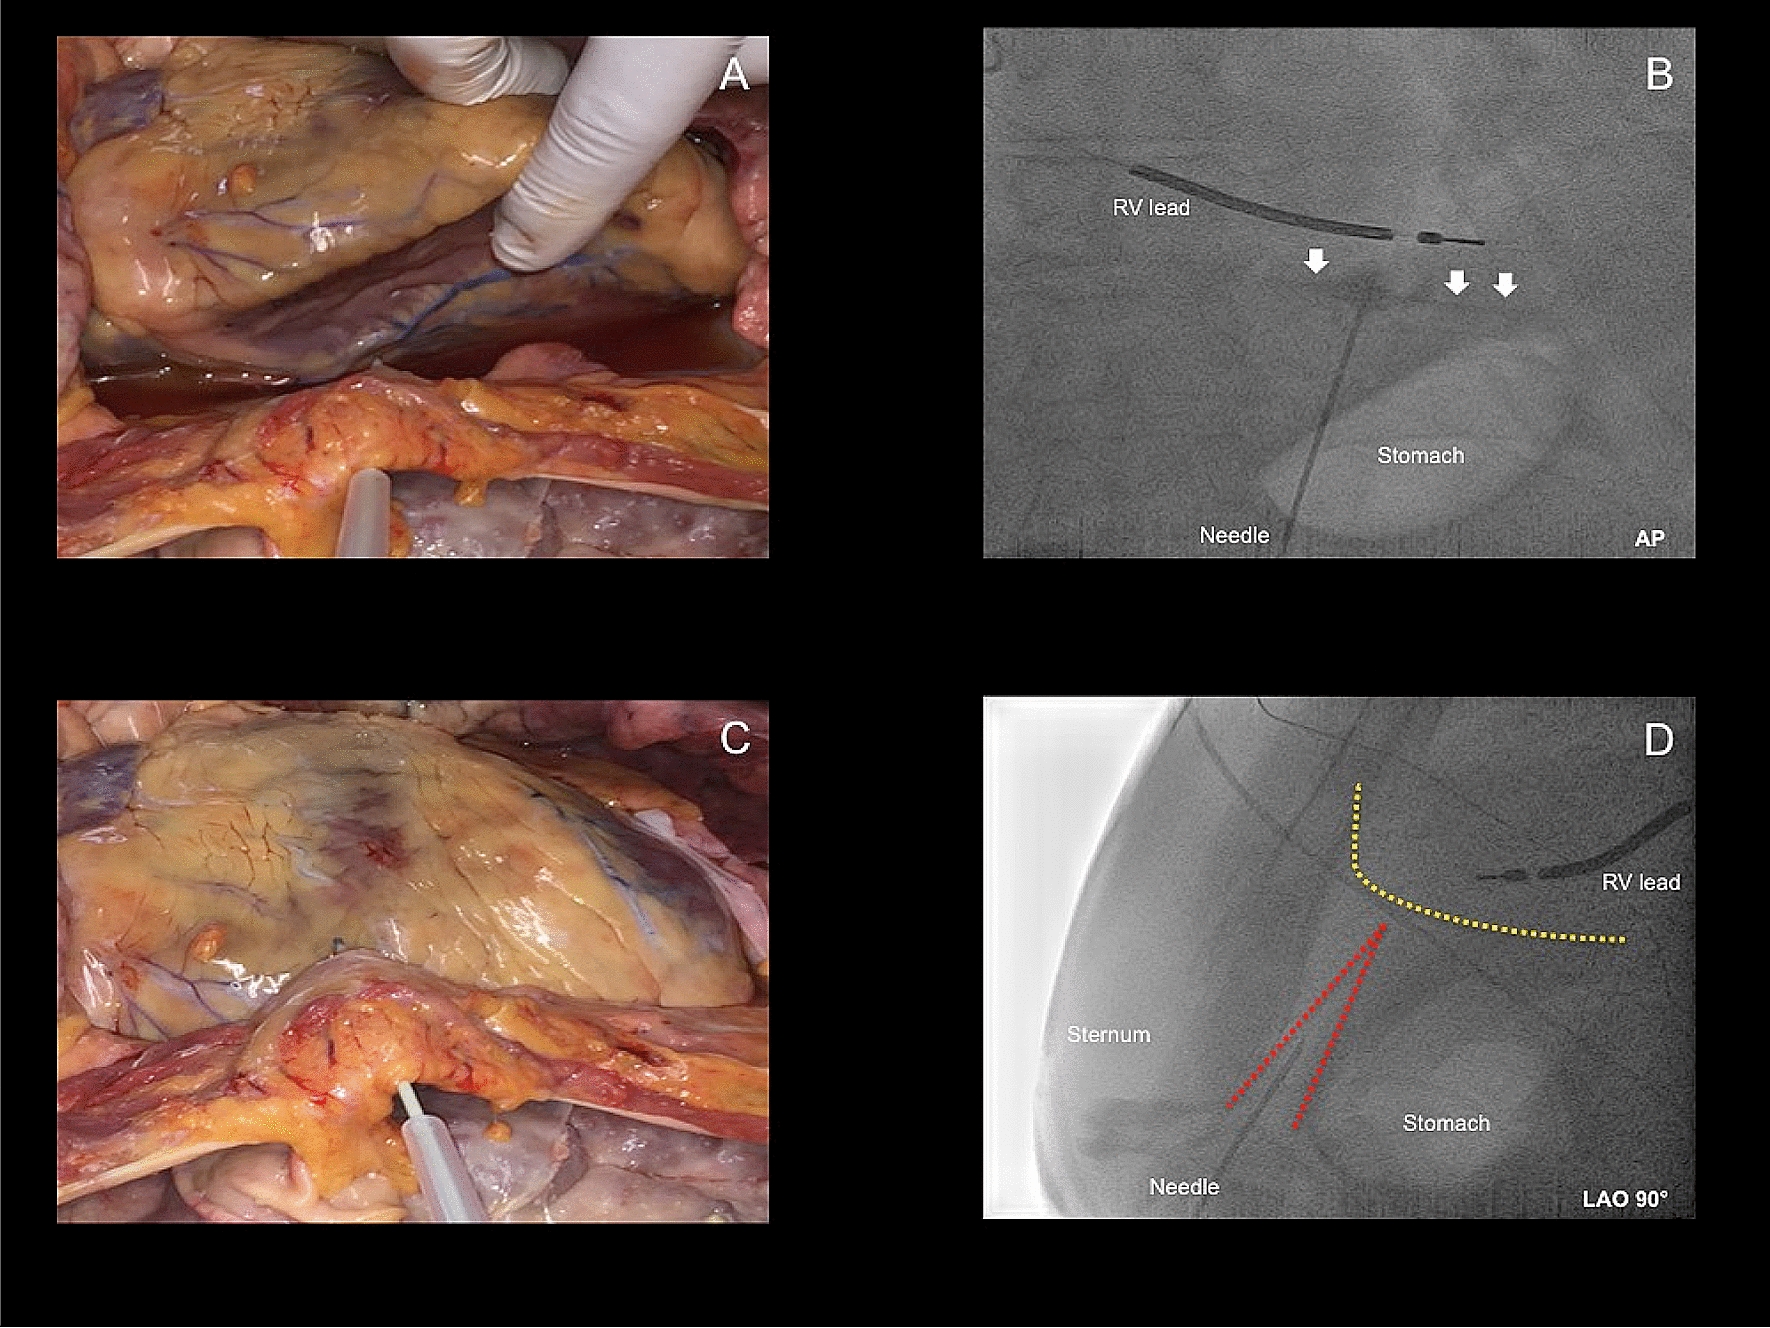

Fig. 2

a, b Inferior epicardial access with fluoroscopy projection in AP. White arrows in b illustrate the contrast media within the pericardial space. c, d Anterior epicardial access with fluoroscopy projection in LAO 90°. Yellow dotted line illustrates the silhouette of the heart. Red dotted line illustrates the triangle between sternum, abdominal organs and heart. With permission of the Institute of Pathology, Asklepios Hospital St. George. LAO Left anterior oblique, AP Anteroposterior, RV right ventricle

Epicardial procedures—inferior approach for epicardial access (group 1)

Epicardial procedures—anterior approach for epicardial access (group 2)

The initially performed inferior-oriented epicardial access approach was modified and changed after February 2012 to an anterior-oriented puncture technique (Figs. 1, 2) due to a remaining high rate of cardiac and non-cardiac complications, as well as first reports about the safety profile of the anterior puncture technique [18, 19]. In this patient cohort, a “dry” subxiphoid puncture was performed under fluoroscopic guidance in AP and LAO 90° view. After initial puncturing of the skin below the xiphoid process, the needle was further maneuvered in a medioclavicular direction towards the pericardial space in LAO 90° guidance to distinguish the triangle of sternum, abdominal organs and right ventricle (Fig. 2d). The needle was slowly advanced directly below the sternum, but above the abdominal organs (Fig. 2d). Remaining steps of pericardial access were the same as in the inferior-oriented puncture group. Again, verification of the correct needle position was performed with contrast media and a long guidewire was advanced to the epicardial space. In addition, dilatation of the puncture side and advancement of a long 8.5F SL-1 or a steerable sheath were the final steps.